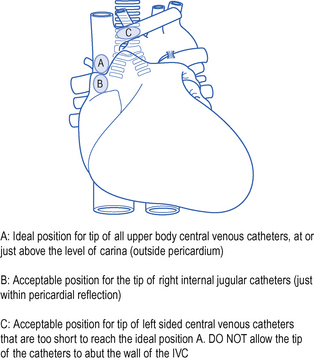

Suture the line into place using the anchorage devices provided and cover with an adhesive sterile dressing. Obtain a CXR to verify position of the line and check for complications, including pneumothorax and haemothorax.

Obtain a CXR to verify position of the line and check for complications, including pneumothorax and haemothorax.Position on chest X-ray

The catheter should lie along the long axis of the vessel and the distal segment and tip should be in the superior vena cava (SVC) or at the junction of the SVC and right atrium but ideally outside the pericardial reflection. Catheters below this level may perforate the heart and cause cardiac tamponade. The pericardial reflection lies below the level of the carina and this can therefore be used as a radiological marker. Catheters placed via subclavian veins of left internal jugular vein must not be allowed to lie with the tip abutting the wall of the superior vena cava. This may cause pain, perforation and accelerated thrombus formation. Either advance the catheter to lie in the long axis of the SVC or pull it back to lie in the brachiocephalic vein. See Fig. 15.4.